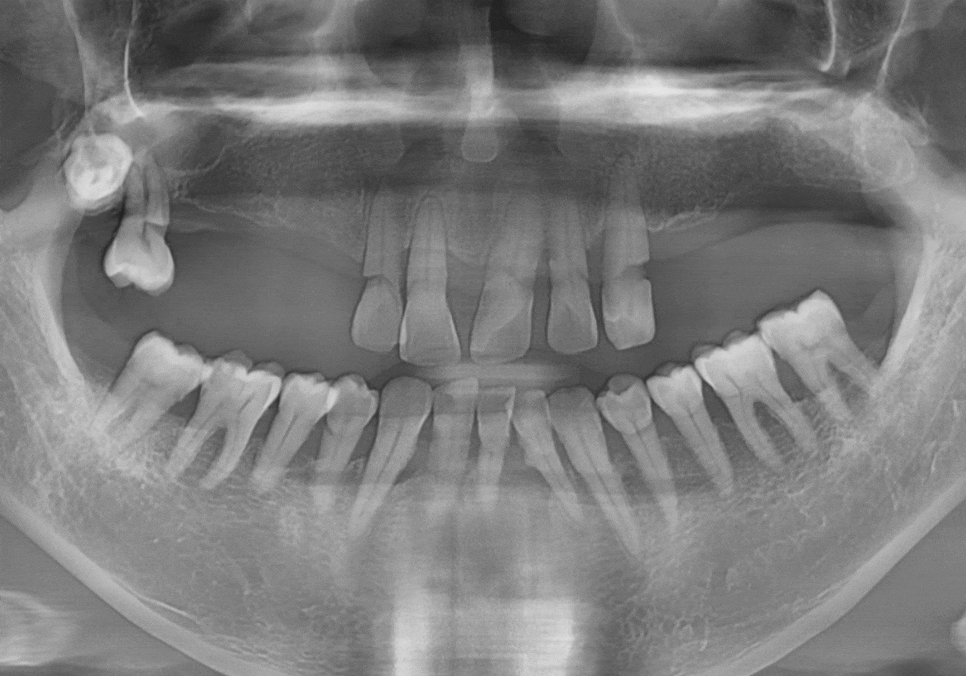

환자분의 구강 상태를 보여주는

파노라마 사진이에요.

언뜻 보셔도 치아가 몇 개 남지 않았다는 걸

금방 아실 텐데요.

위턱과 아래턱 모두 치아가 많이 빠져있고,

그나마 남아있는 치아들도 상태가 좋지 않았습니다.

치아를 잡아주는 잇몸뼈(치조골)가 많이

녹아내려 있었거든요.

특히, 틀니 고리가 걸리는 치아들에

너무 많은 힘이 쏠리다 보니,

뿌리 쪽이 심하게 패어

몹시 약해진 상태였습니다.

이렇게 되면 틀니를 아무리 새로 맞춰도

잇몸만 아프고 제대로 씹기가 참 힘듭니다.

사진 오른쪽 끝을 보시면 #18번 사랑니가

하나 매복되어 있는 게 보이실 거예요.

이 사랑니는 이미 뼈 안쪽

깊숙이 자리 잡고 있어서,

환자분께 가장 무리가 가지 않는 방향으로

매복된 상태로 두기로 했습니다.

이번 케이스는 사랑니를 제외한 치아를 모두

발치하고 총 7대의 임플란트를 심기로 했습니다.